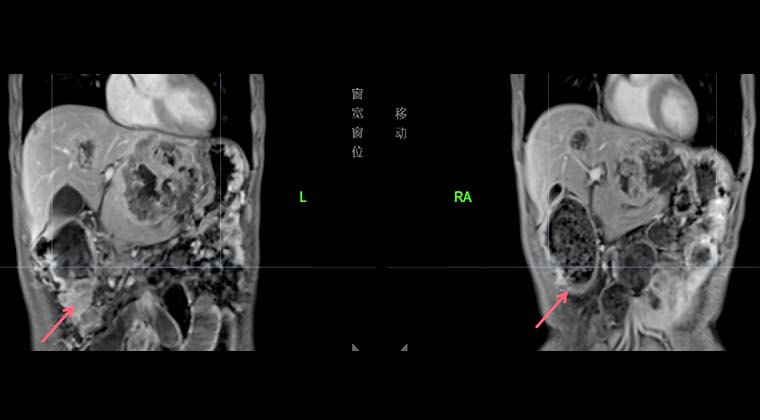

Пациент, мужчина, 75 лет, умеренно дифференцированная аденокарцинома поперечной ободочной кишки, с метастазами в печень и кости.

(Молекулярное тестирование: мутация KRAS p.G12V; BRAF V600E – дикий тип; TMB 2,9; MSS; PD-L1 отрицательный)

Жалобы и ход заболевания: С мая 2024 года наблюдалось потемнение кала (черновато-зеленого цвета), затем прогрессирующая слабость. Обследование в другой клинике показало тяжелую анемию (HGB ~40 г/л), визуализационные методы выявили опухоль ободочной кишки с вероятными множественными метастазами. Биопсия подтвердила умеренно дифференцированную аденокарциному поперечной ободочной кишки. Пациент направлен в нашу больницу для оценки PET/CT, что подтвердило поперечную аденокарциному с множественными метастазами в печень и кости.

План лечения: Под контролем DSA проведена артериальная интервенционная терапия вокруг питающих артерий опухоли (суперселективная ангиография + эмболизация питающей артерии + артериальная инфузионная химиотерапия), проведена 4 сессии: 07-26, 08-26, 10-16 и 11-0 Схема артериальной инфузии включала оксалиплатин (100 мг) в комбинации с пероральным капецитабином (1 г, дважды в день, d1–14) для паллиативной химиотерапии.

Эффект лечения и наблюдение: Контрольное обследование 10-14 показало значительное уменьшение первичной опухоли поперечной кишки; анемия улучшилась, общее состояние пациента стабилизировалось и также заметно улучшилось.

Левое изображение: 2024-08-20, опухоль поперечной ободочной кишки

Правое изображение: 2024-10-14, опухоль поперечной ободочной кишки значительно уменьшилась, анемия пациента заметно улучшилась

Левое изображение: 2024-08-20, множественные очаги в печени

Правое изображение: 2024-10-14, очаги в печени заметно уменьшились и стали меньше по числу